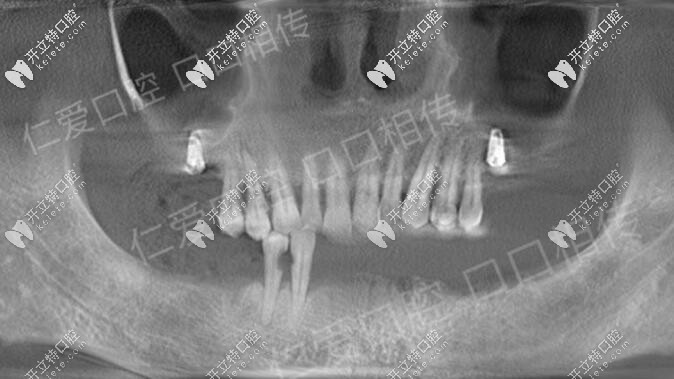

諾貝爾ALL-ON-6即刻負重種植牙馬上有牙,武漢人都來這種牙

諾貝爾即刻種植即刻負重種植牙,無牙頜顧客的福音,ALL-ON-6即刻負重,植入6顆種植體就可種出整排牙。

3d導板+all-on-6半口即刻負重,讓武漢老人當天種植牙當天用

多顆缺失、半口牙缺失老人如何種牙?大波圖,了解下3d導板即刻負重半口種植牙技術,當天種牙,當天用。

武漢私立牙科all-on6半口種植牙成功,登騰價格便宜老人夠用了

在仁愛醫(yī)院口腔給老爸做了ALL-ON-6下半口種植牙,上半口口種了2顆,這家醫(yī)院的韓系登騰種植體收費還是挺親民的,給老人種完全夠用了。